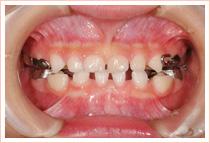

不正咬合の症例

上の写真で見られるように、顎の骨の発育不全によって、歯並び・噛み合わせが悪くなってしまっています。

原因として、顎の成長が上顎で抑えられ、顎の発達が妨げられているということが考えられます。